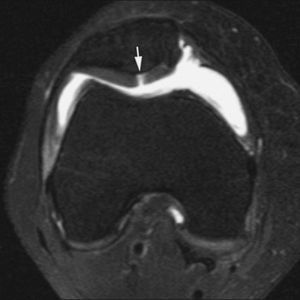

El síndrome de choque anterior es una causa relativamente frecuente de dolor crónico de tobillo, especialmente en deportistas sometidos a estrés repetido del tobillo en dorsiflexión («tobillo de futbolista»). Este proceso produce la existencia de prominencias óseas en el margen anterior del techo tibial, generalmente asociadas a otras en el área correspondiente sobre el margen opuesto del astrágalo. Estos osteofitos pueden chocar entre sí, especialmente con la dorsiflexión del tobillo, y atrapar tejidos de partes blandas. La RMA es de gran utilidad en la valoración de la afectación condral y la sinovitis (fig. 11) en el receso capsular anterior del tobillo19,23.

Fig. 10.--Síndrome de choque antero-lateral. Corte axial de RMA potenciado en T1 que muestra un tejido fibroso irregular ocupando el receso capsular antero-lateral (flechas).